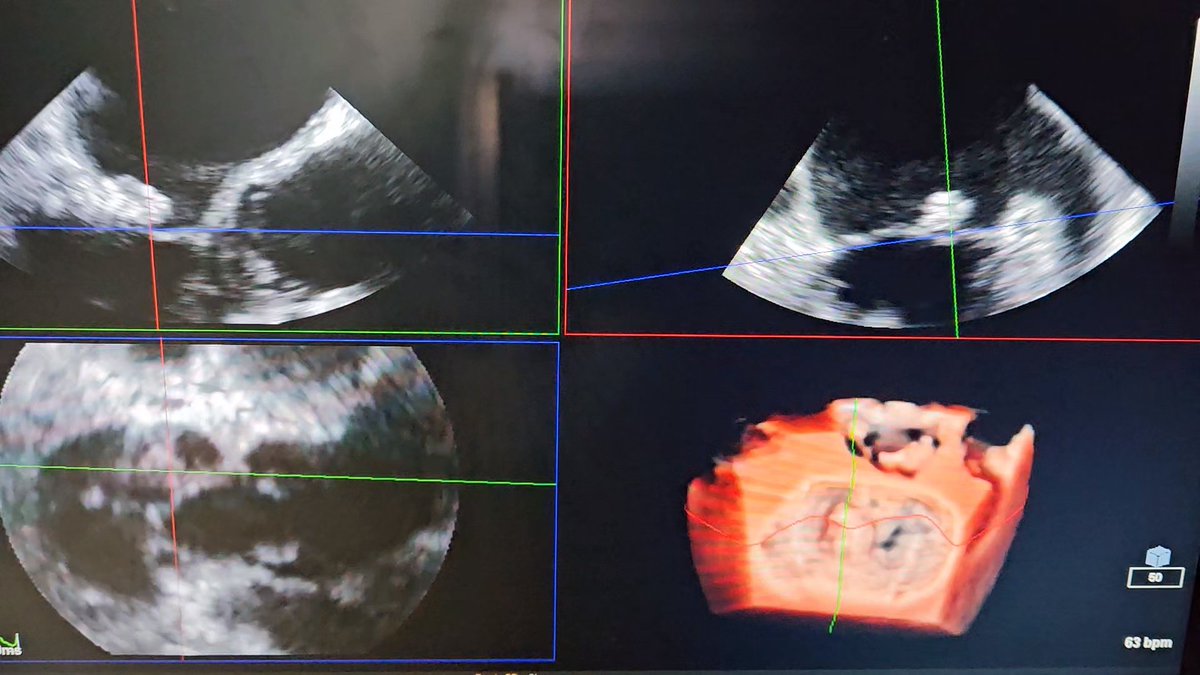

THE ❌ VALVE

4-leaflets #tricuspid valve with massive regurgitation.

#echocardiography #echofirst #3Decho #tricuspidvalve #tricuspidregurgitation #cardiology